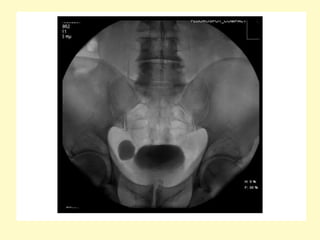

Intravenous urogram showing right-sided hydronephrosis and the

dilation of the proximal ureter up to the level of the L3 transverse

process, the medial deviation of the ureter at this level (arrow) gives

rise to the typical fish hook or reversed S appearance

Intravenous urogram showingright-sided hydronephrosis and the dilation of the proximal ureter up to the level of the L3 transverse process, the medial deviation of the ureter at this level (arrow) gives rise to the typical fish hook or reversed S appearance